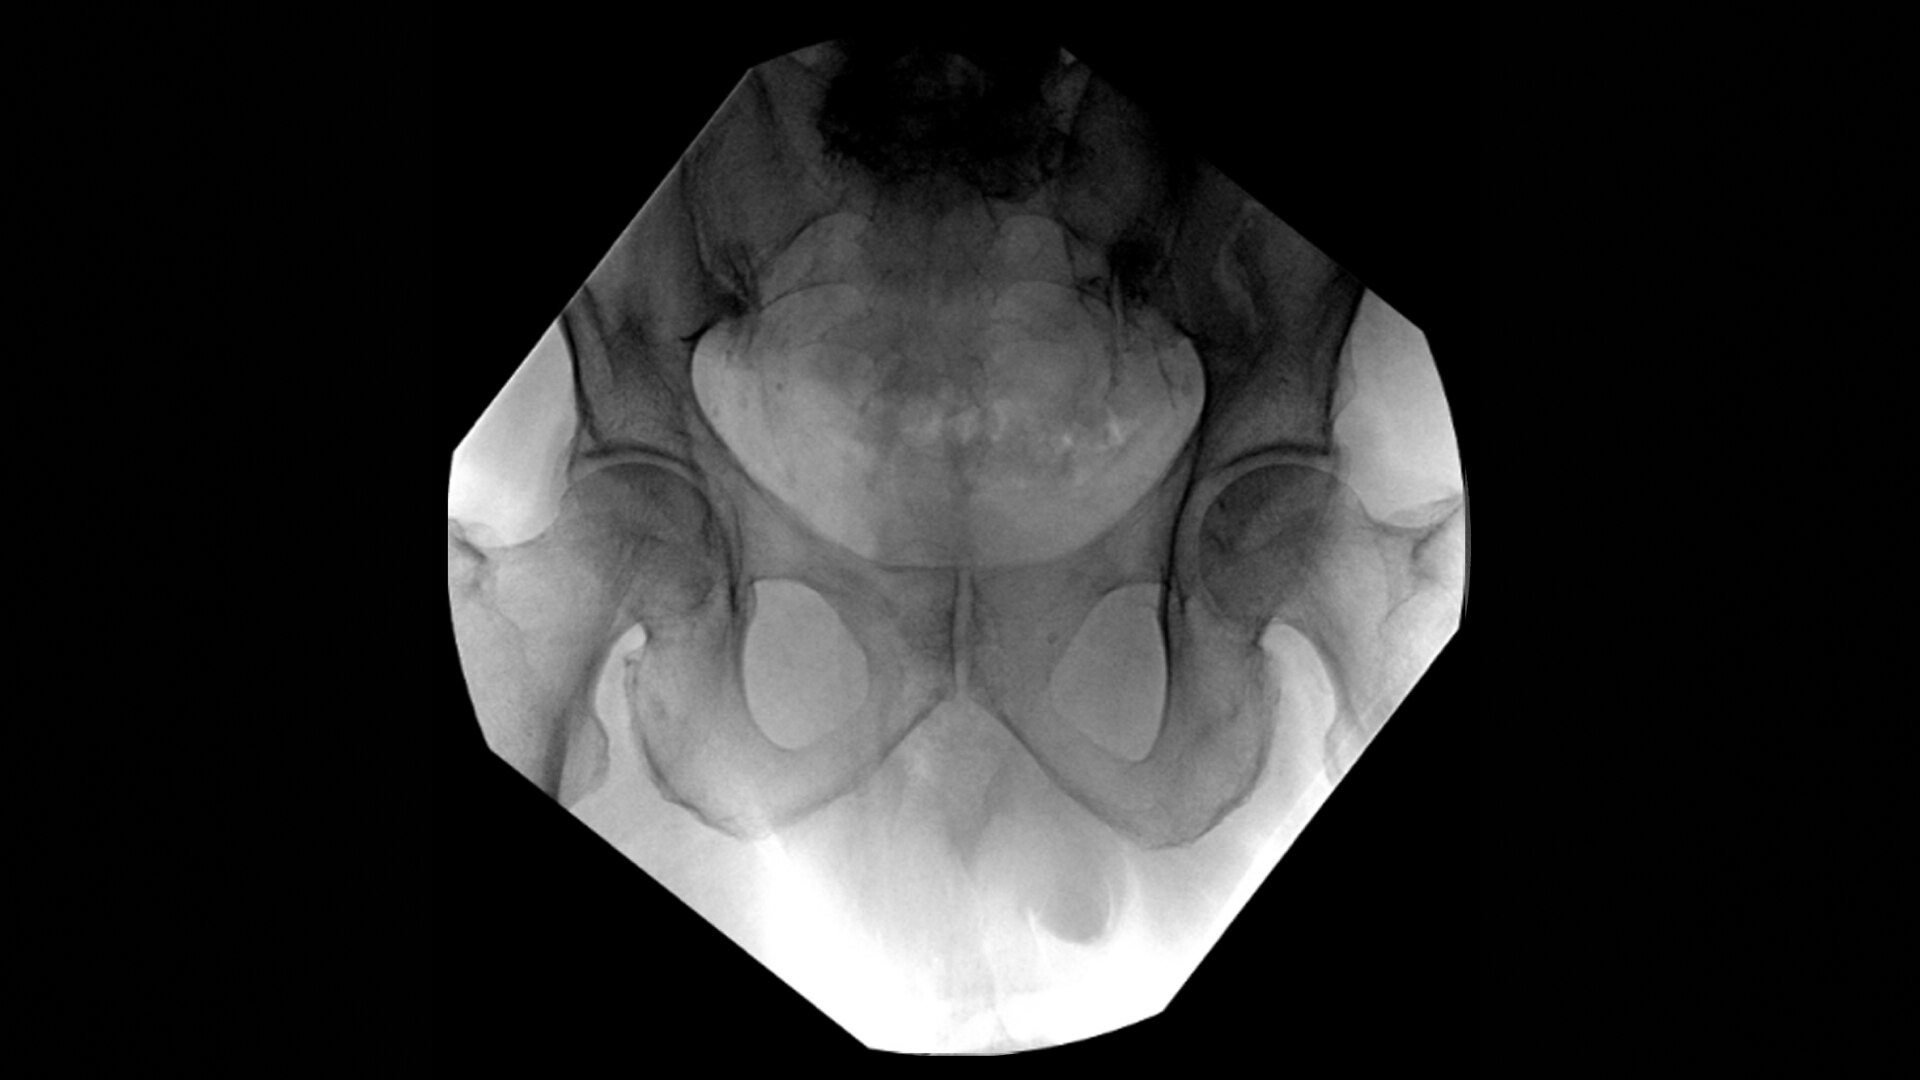

OEC C-arms provide orthopedic imaging with a large field of view optimized to clearly visualize orthopedic anatomy, such as the entire long bone femur or minute fractures in extremities. A clear display with comfortable viewing can easily show AP and lateral views, enabling efficient procedure planning.

During hip or femur imaging, capture up to 22% more Field of View by positioning detector closer to patient anatomy with the OEC low-profile X-ray tube housing compared to mono-block C-arms.

Complex orthopedic procedures require powerful imaging systems. OEC premium C-arms perform in a variety of procedures such as:

• Hip fracture fixation

• Hip replacement